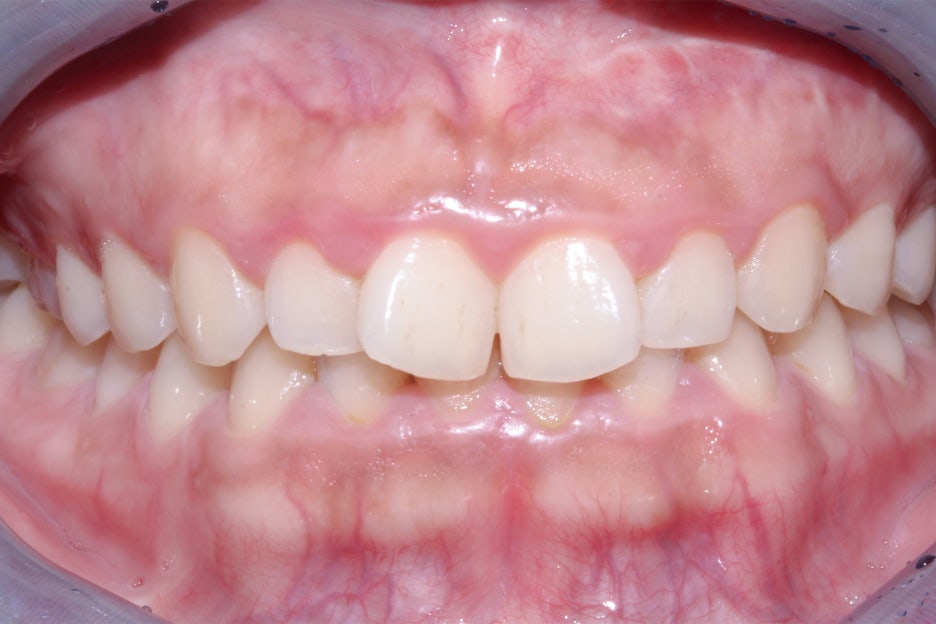

교정 시작 후 약 5개월 경과 후 모습입니다.

삐뚤거리던 전치부의 치아들이 가지런하게

배열된 것을 확인할 수 있는데요,

나비치아 증상을 보이던 중절치도

바른 치축으로 교정된 모습입니다.

세라믹교정 종료 후 스마일라인의 모습입니다.

노출되는 상악 전치부 치아들이 교정 전보다

한결 가지런해진 모습으로 회전되었던

중절치의 변화가 특히 극적인 모습인데요,

전치부의 측면 사진에서도 나비치아 증상이

사리지고 바른 각도록 교정된 중절치를 확인할 수 있습니다.

구내사진을 보시면 브라켓을 부착했던 치아들이

모두 고르게 배열된 모습인데요, 부분교정의 경우